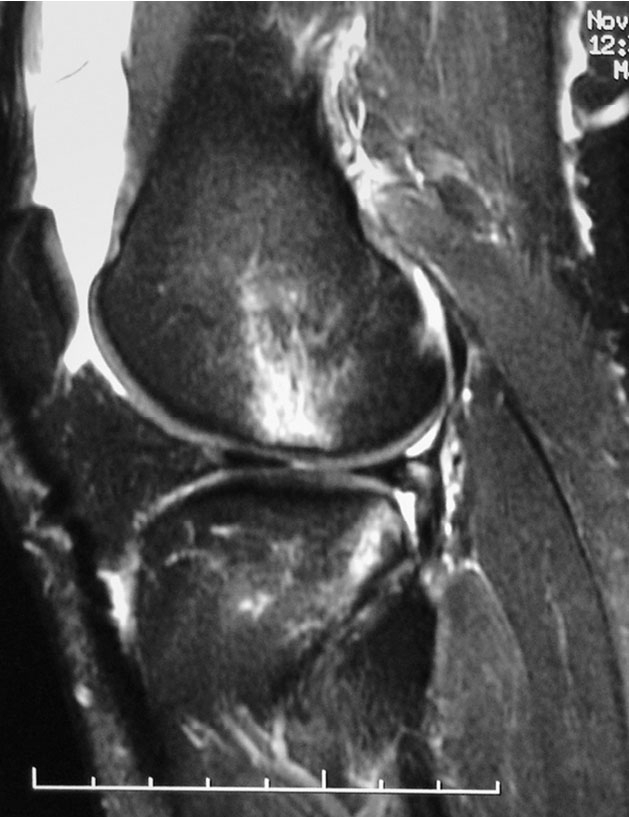

前交叉韧带慢性损伤的磁共振成像

A.前交叉韧带信号消失;B.前交叉韧带信号不规则;C.前交叉韧带信号移位

前交叉韧带慢性损伤的磁共振影像表现为三种情况:信号消失、信号不规则和信号移位。前交叉韧带损伤后韧带组织被完全吸收,磁共振成像上则表现为信号消失。

前交叉韧带损伤后有残存的少量纤维和瘢痕组织被滑膜包绕,即为信号不规则,它包括信号密度不均、粗细不均、迂曲无张力等。信号移位是指前交叉韧带自股骨止点撕脱后瘢痕粘连在后交叉韧带上。